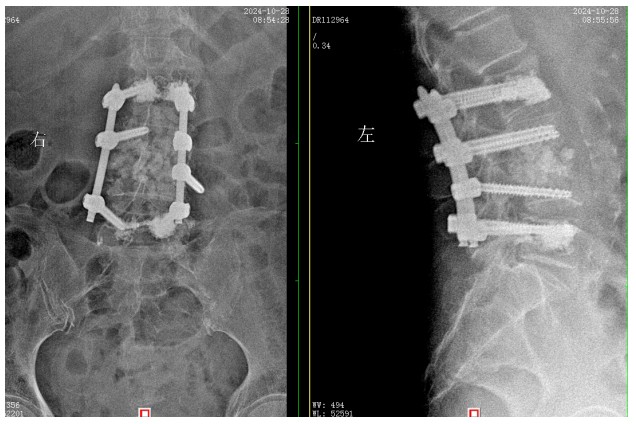

經(jīng)過積極充分的準(zhǔn)備,錢軍博士團(tuán)隊(duì)為患者成功實(shí)施了L3���、L4脊柱結(jié)核病灶清除植骨融合內(nèi)固定術(shù)��,手術(shù)順利�,術(shù)后患者腰腿痛癥狀明顯緩解����,患者及家屬對(duì)治療效果非常滿意,對(duì)醫(yī)院的醫(yī)療技術(shù)以及優(yōu)質(zhì)的服務(wù)護(hù)理稱贊不已����。